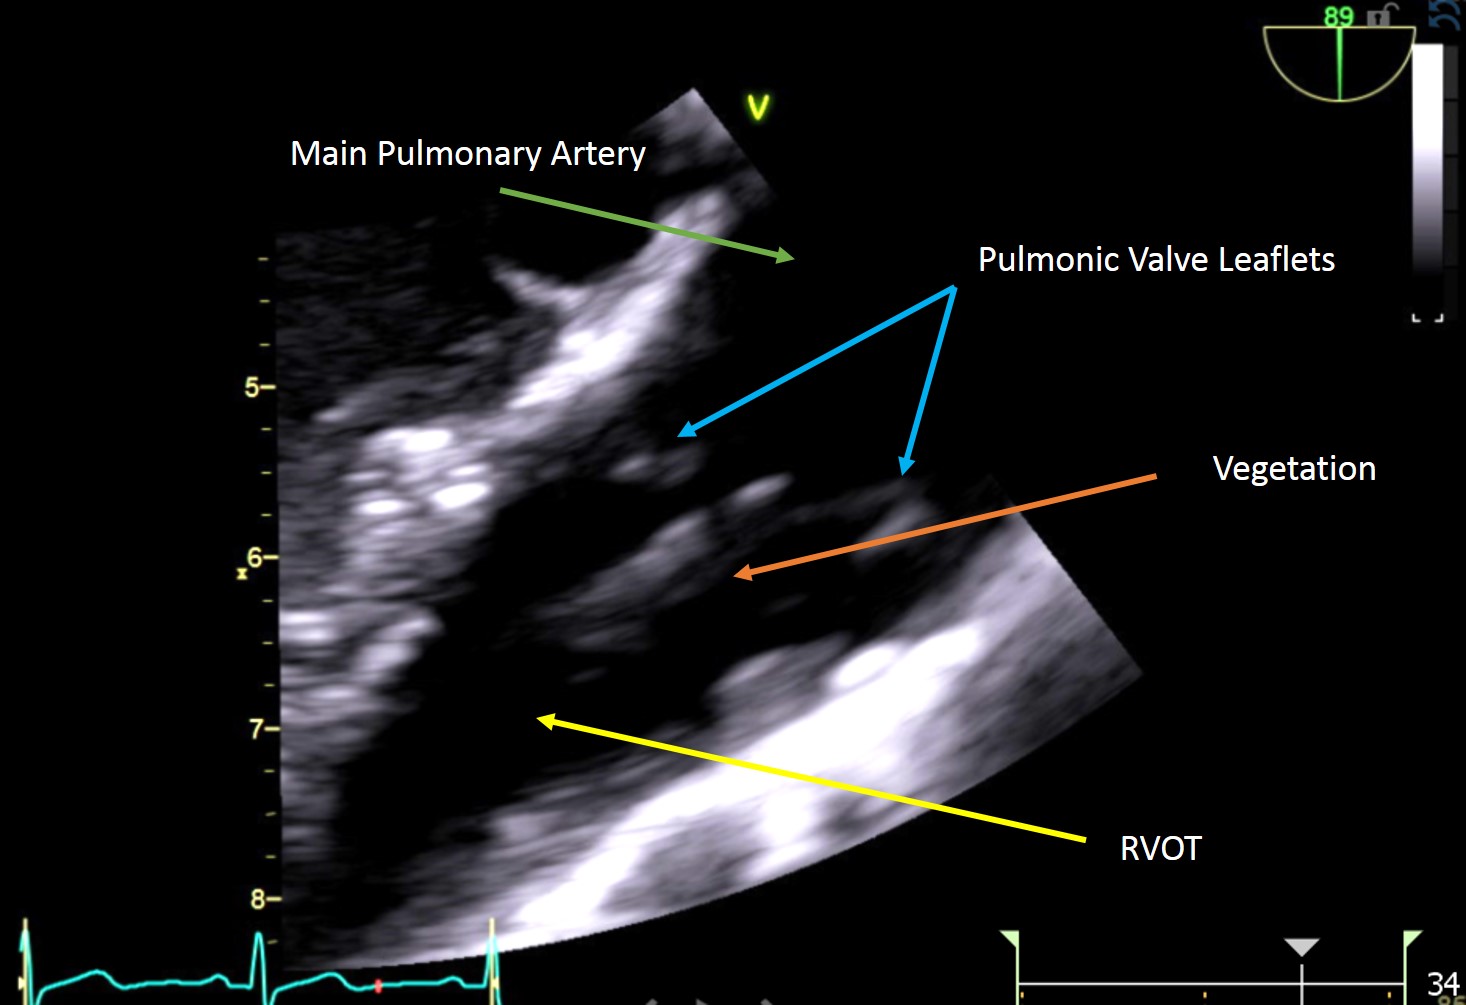

Case Presentation: 27 year old Caucasian female admitted with fever, abdominal pain radiating to back. She was not an IV drug user. Has a recent history of facial abscess following spider bite but no signs of cellulitis over extremities. There was a small red spot on lower right eyelid, no Osler nodes, janeway lesions, no track marks, no murmur. Blood cultures were positive for MRSA. Patient was started on vancomycin. CT Abdomen and Pelvis showed Nodular tree in bud parenchyma. CT-chest showed Cavitary lesion which raised suspicion of infectious process. MRI –spine showed Epidural abscess. . In order to further evaluate the infectious process TEE was done that showed competent, perivalvular, moderate pulmonary valve vegetation. She was hence diagnosed with pulmonic valve endocarditis complicated by septic pulmonary emboli and epidural abscess. She was managed medically and had lumbar spine epidural abscess drainage and L3-L4 laminotomy. Her high grade MRSA bacteremia was treated with 6 weeks of vancomycin. It made it a unique case of Spider bite induce Inf. Endocarditis and involvement of pulmonary valve that is rare.

Most native-valve endocarditis involves the tricuspid valve. Hence pulmonary valve endocarditis without involvement of the tricuspid valve is extremely rare, with fewer than 90 reported cases. Most present with pulmonary valve regurgitation, however in our patient the valve remained competent.